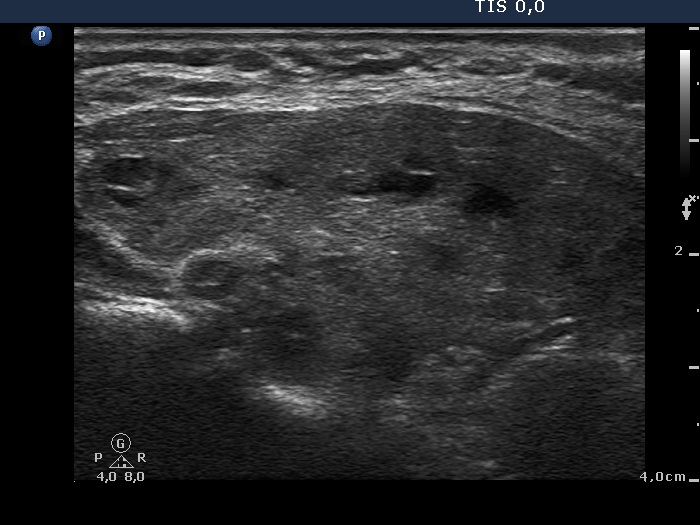

Consecutively operated patients with autoimmune thyroid disease - case 8 (409) (ultrasonographic picture 5)

Left lobe, longitudinal scan. The cystic areas correspond to dilated macrofollicles.